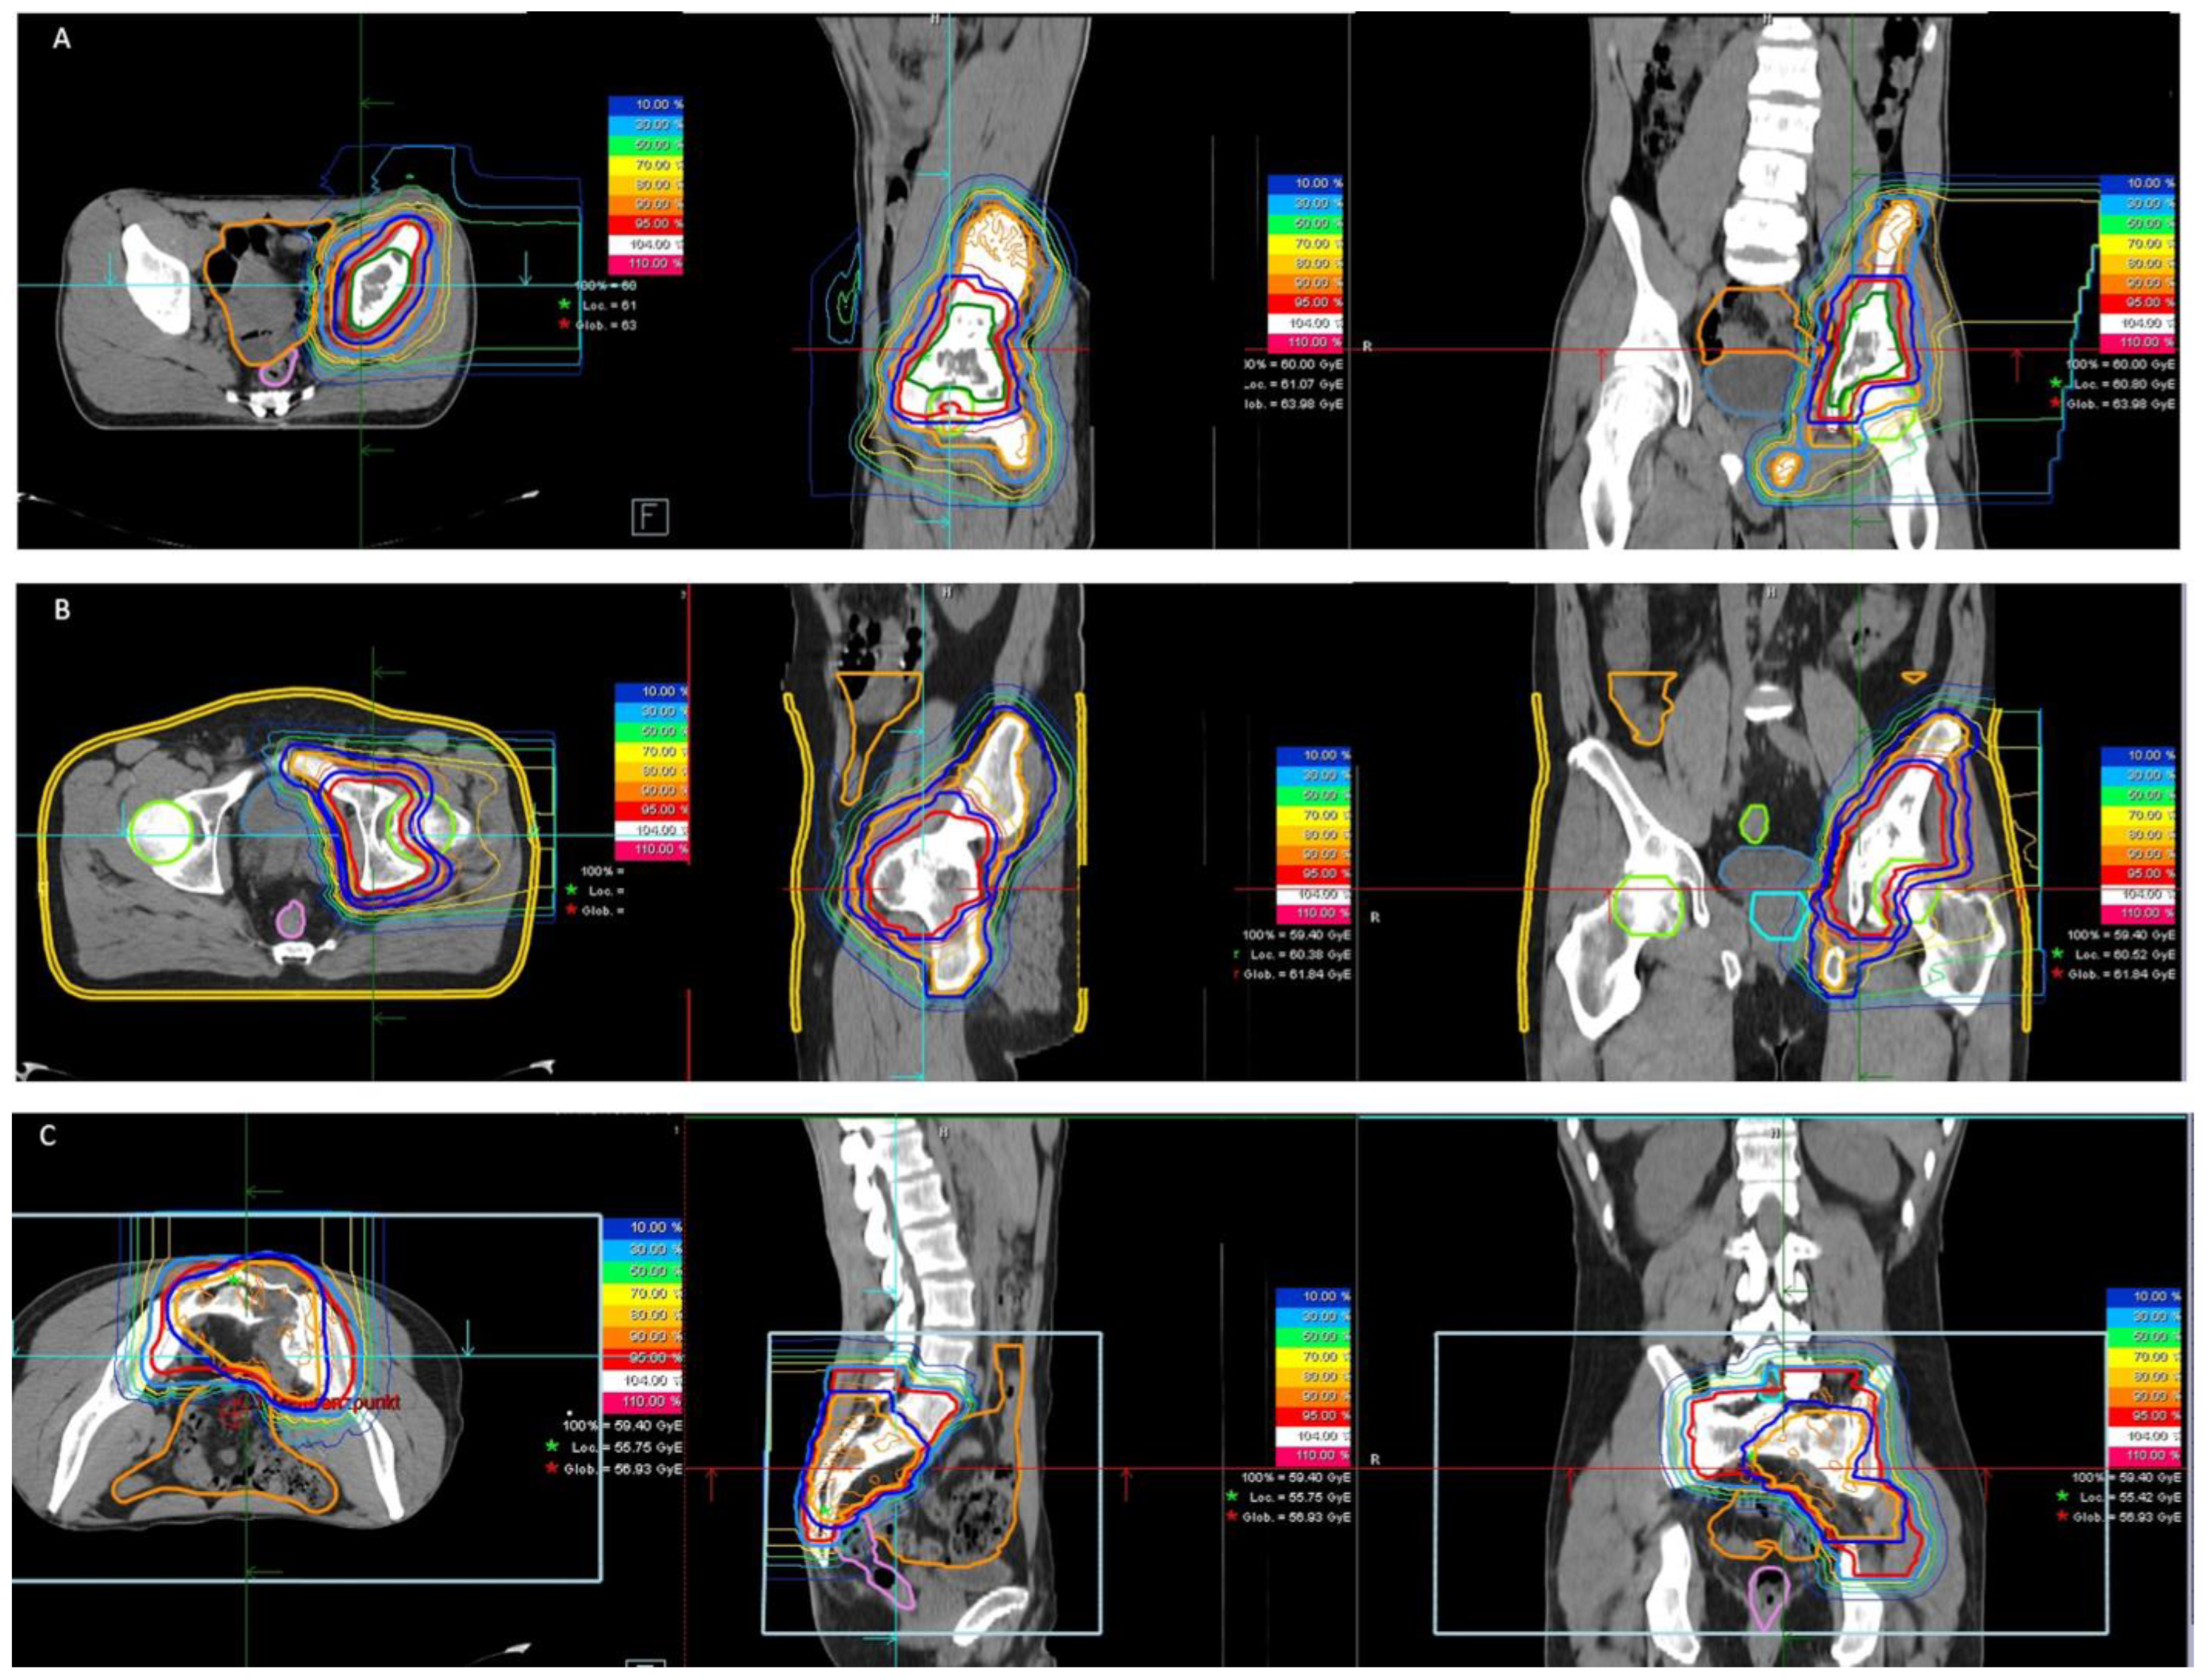

2.2. Radiotherapy

| Type of radiotherapy (n) | ||

| proton | 18 | |

| carbon ion | 3 |

| Proton | VMAT | p-Value | ||

| median total prescribed dose (range) in Gy (RBE) | 59.4 (54–60) | |||

| median single prescribed dose (range) in Gy (RBE) | 1.8 (1.5 *–2) | |||

| Primary tumor treated in adjuvant setting (protons) | n = 3 | |||

| median total prescribed dose (range) in Gy (RBE) | 45 (45–54) | |||

| median single prescribed dose (range) in Gy (RBE) | 1.8 (1.8) | |||

| Recurrent tumor treated in definitive/additive/ adjuvant setting (carbon ions) | n = 3 | |||

| median total prescribed dose (range) in Gy (RBE) | 51 | |||

| median single prescribed dose (range) in Gy (RBE) | 3 | |||